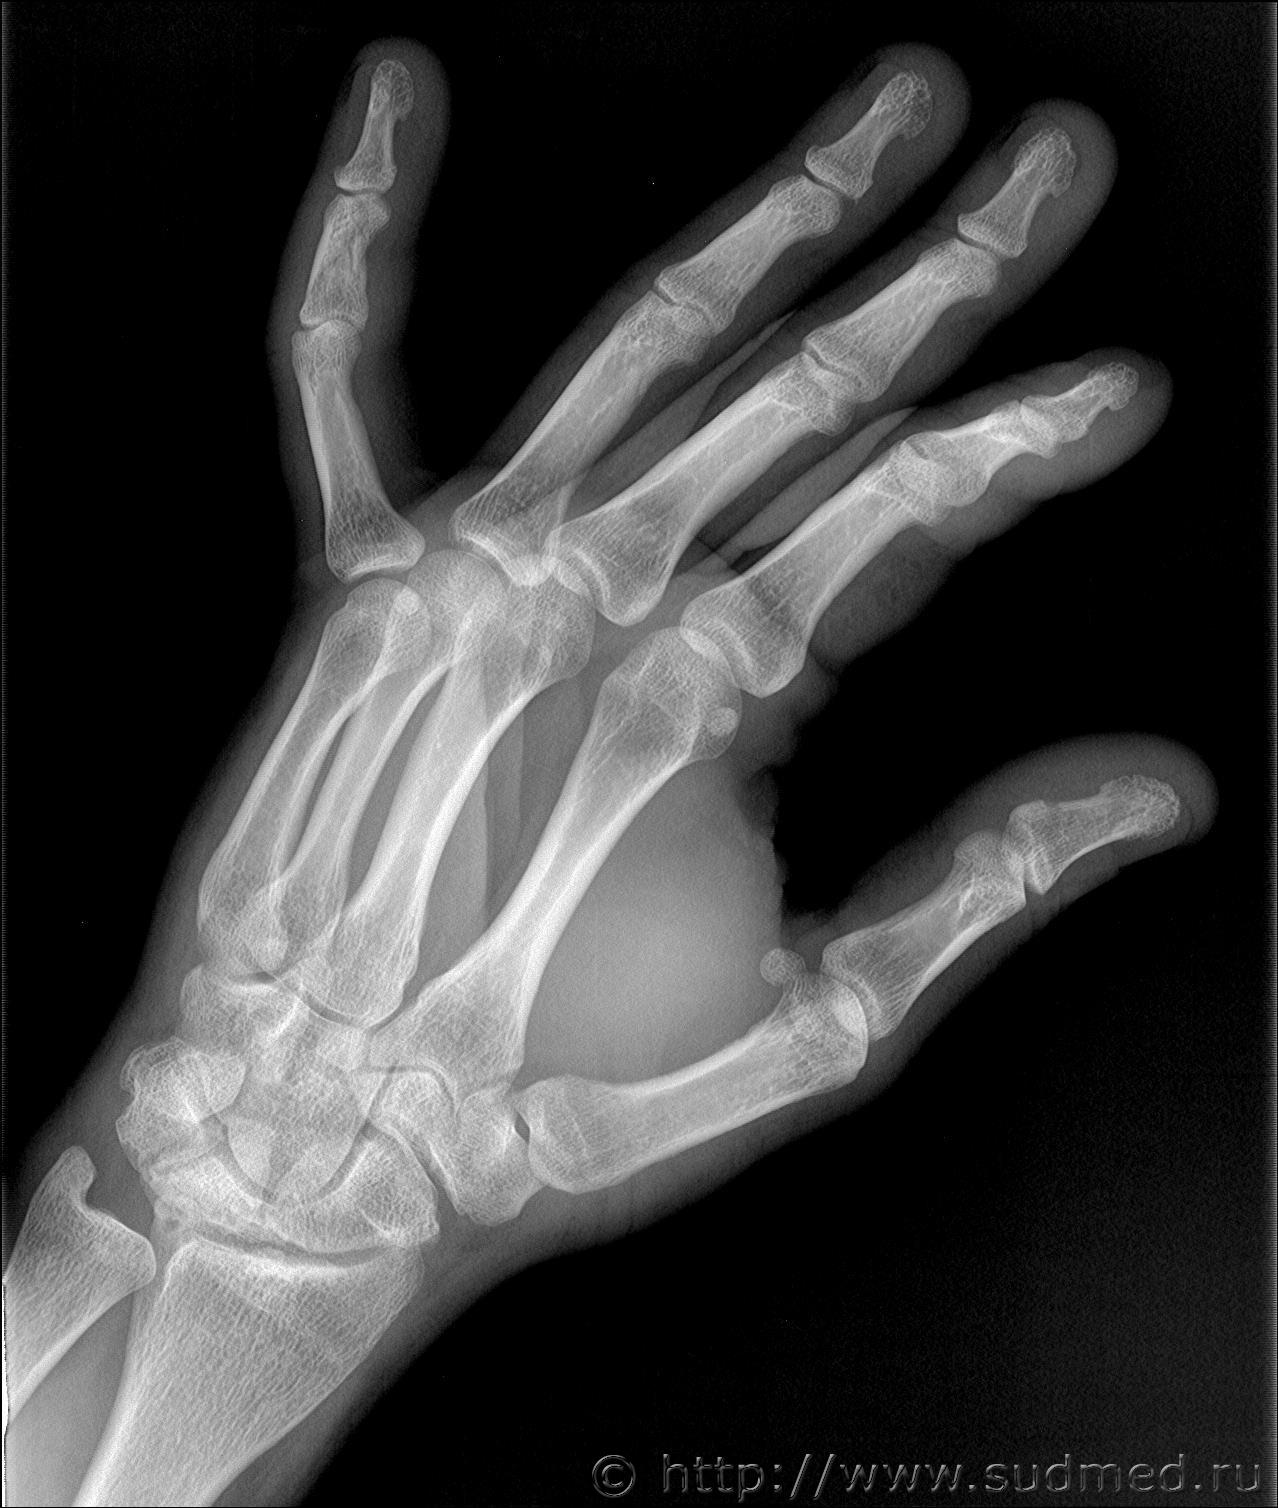

Здравствуйте. Произошла драка в которой когда я упал и меня пинали по голове, я закрыл голову рукой и нападавший попал ногой по руке. В результате он повредил мне мизинец на левой руке. Врач скорой сказала что это скорее всего ушиб. Я думал что ушиб пройдет, но палец болел и через 13 дней я обратился в травмпункт, мне сделали рентген кисти и обнаружили «З/консолидирующийся перелом о/фаланги Vп левой кисти». По этой справке мне определили средний вред здоровью. Потом когда суд мед эксперты смотрели данный снимок они не нашли перелома. Снимок сделан в травм пункте на 13 день после травмы. Можете ли вы оценить снимки. Что на них видно? Какая степень вреда здоровью?

Скорее всего технический сбой. Вот изображения в другом формате.

Достоверно перелома не видно.

Еще один снимок делал но там 3 месяца прошло и он на пленке. А почему достоверно перелома не видно? Травматолог и глав врач травматологии сказали что точно перелом.

В справке из травм пункта на 13 день после травмы указано:

Установлен диагноз: З/консолидирущийся перелом о/фаланги Vп левой кисти.

По поводу первого снимка, 13 дней после травмы. На диске, цифровой.

Заключение: на представленных рентгенограммах 5 пальца левой кисти от (13 дней после травмы) на электронном носителе костно-травматических изменений не выявляется.

Снимки цифровые 13 дней после травмы:

Больше вопросов и предположений вызывает не основная, а средняя фаланга. Если бы она так выглядела через 100 дней после травмы, можно было бы согласиться, что несколько месяцев назад был перелом средней фаланги. Через 13 дней перелом так выглядеть не может. Вероятно, имеется какая-то индивидуальная особенность или когда-то давно (многие месяцы-годы назад) был перелом средней фаланги мизинца. Основная фаланга особых вопросов не вызывает: согласен с рентгенологами по поводу отсутствия достоверных рентгенологических признаков перелома.